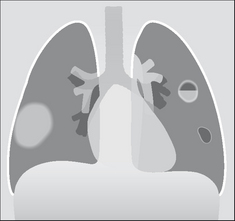

QUESTION 6—IS THERE LUNG CONTUSION?

Contusion is very common following a violent injury. It appears as an area of consolidation, similar in appearance to lobar pneumonia.

image The consolidation2,3,5,13 may:

image Be present on the initial CXR. Usually, it will be evident within six hours of the injury.

image Cavitate.

image Take four to six weeks to clear. Clearing can be particularly slow if contusion has been accompanied by a laceration through the lung parenchyma.

image NB: the differential diagnosis for an area of consolidation on the CXR:

image Lung contusion.

image Aspiration pneumonia.

image Adult respiratory distress syndrome.

image Fat embolism.

image A combination of any of the above.

image

Figure 32.14 Blunt trauma. Lung contusion. Various appearances may result: an area of consolidation (right lung); or cavitation; or a cystic area, i.e. a pneumatocoele (left lung).